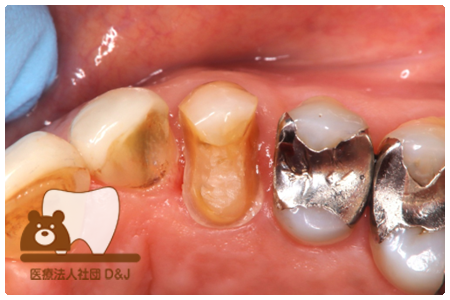

症例3フリジルコニアクラウン 左上6

治療前

治療後

59歳 男性

- 治療内容

- 虫歯で大きく失われた歯に対して、土台としてファイバーコアを使用し、その上にフルジルコニア製の被せ物を装着しました。見た目と強度を両立した自由診療の治療です。

- 治療期間

- 根の治療含めて3カ月半

- 費用

- 自費

フリジルコニアクラウン:77,000円(税込)

(R8.2月時点)

- その他の治療の費用は含まれておりません。

- リスク・副作用

- 強い力が加わると割れる可能性があります。また、噛み合わせや歯ぎしりの影響で脱離することがあります。